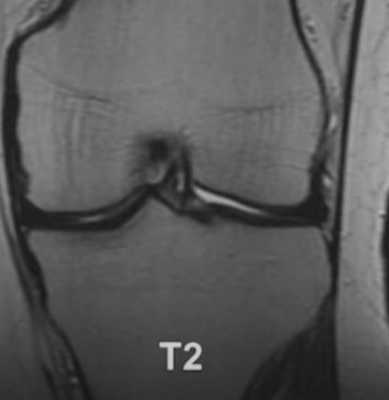

МР-снимок коленного сустава в режиме Т2, контузия кости